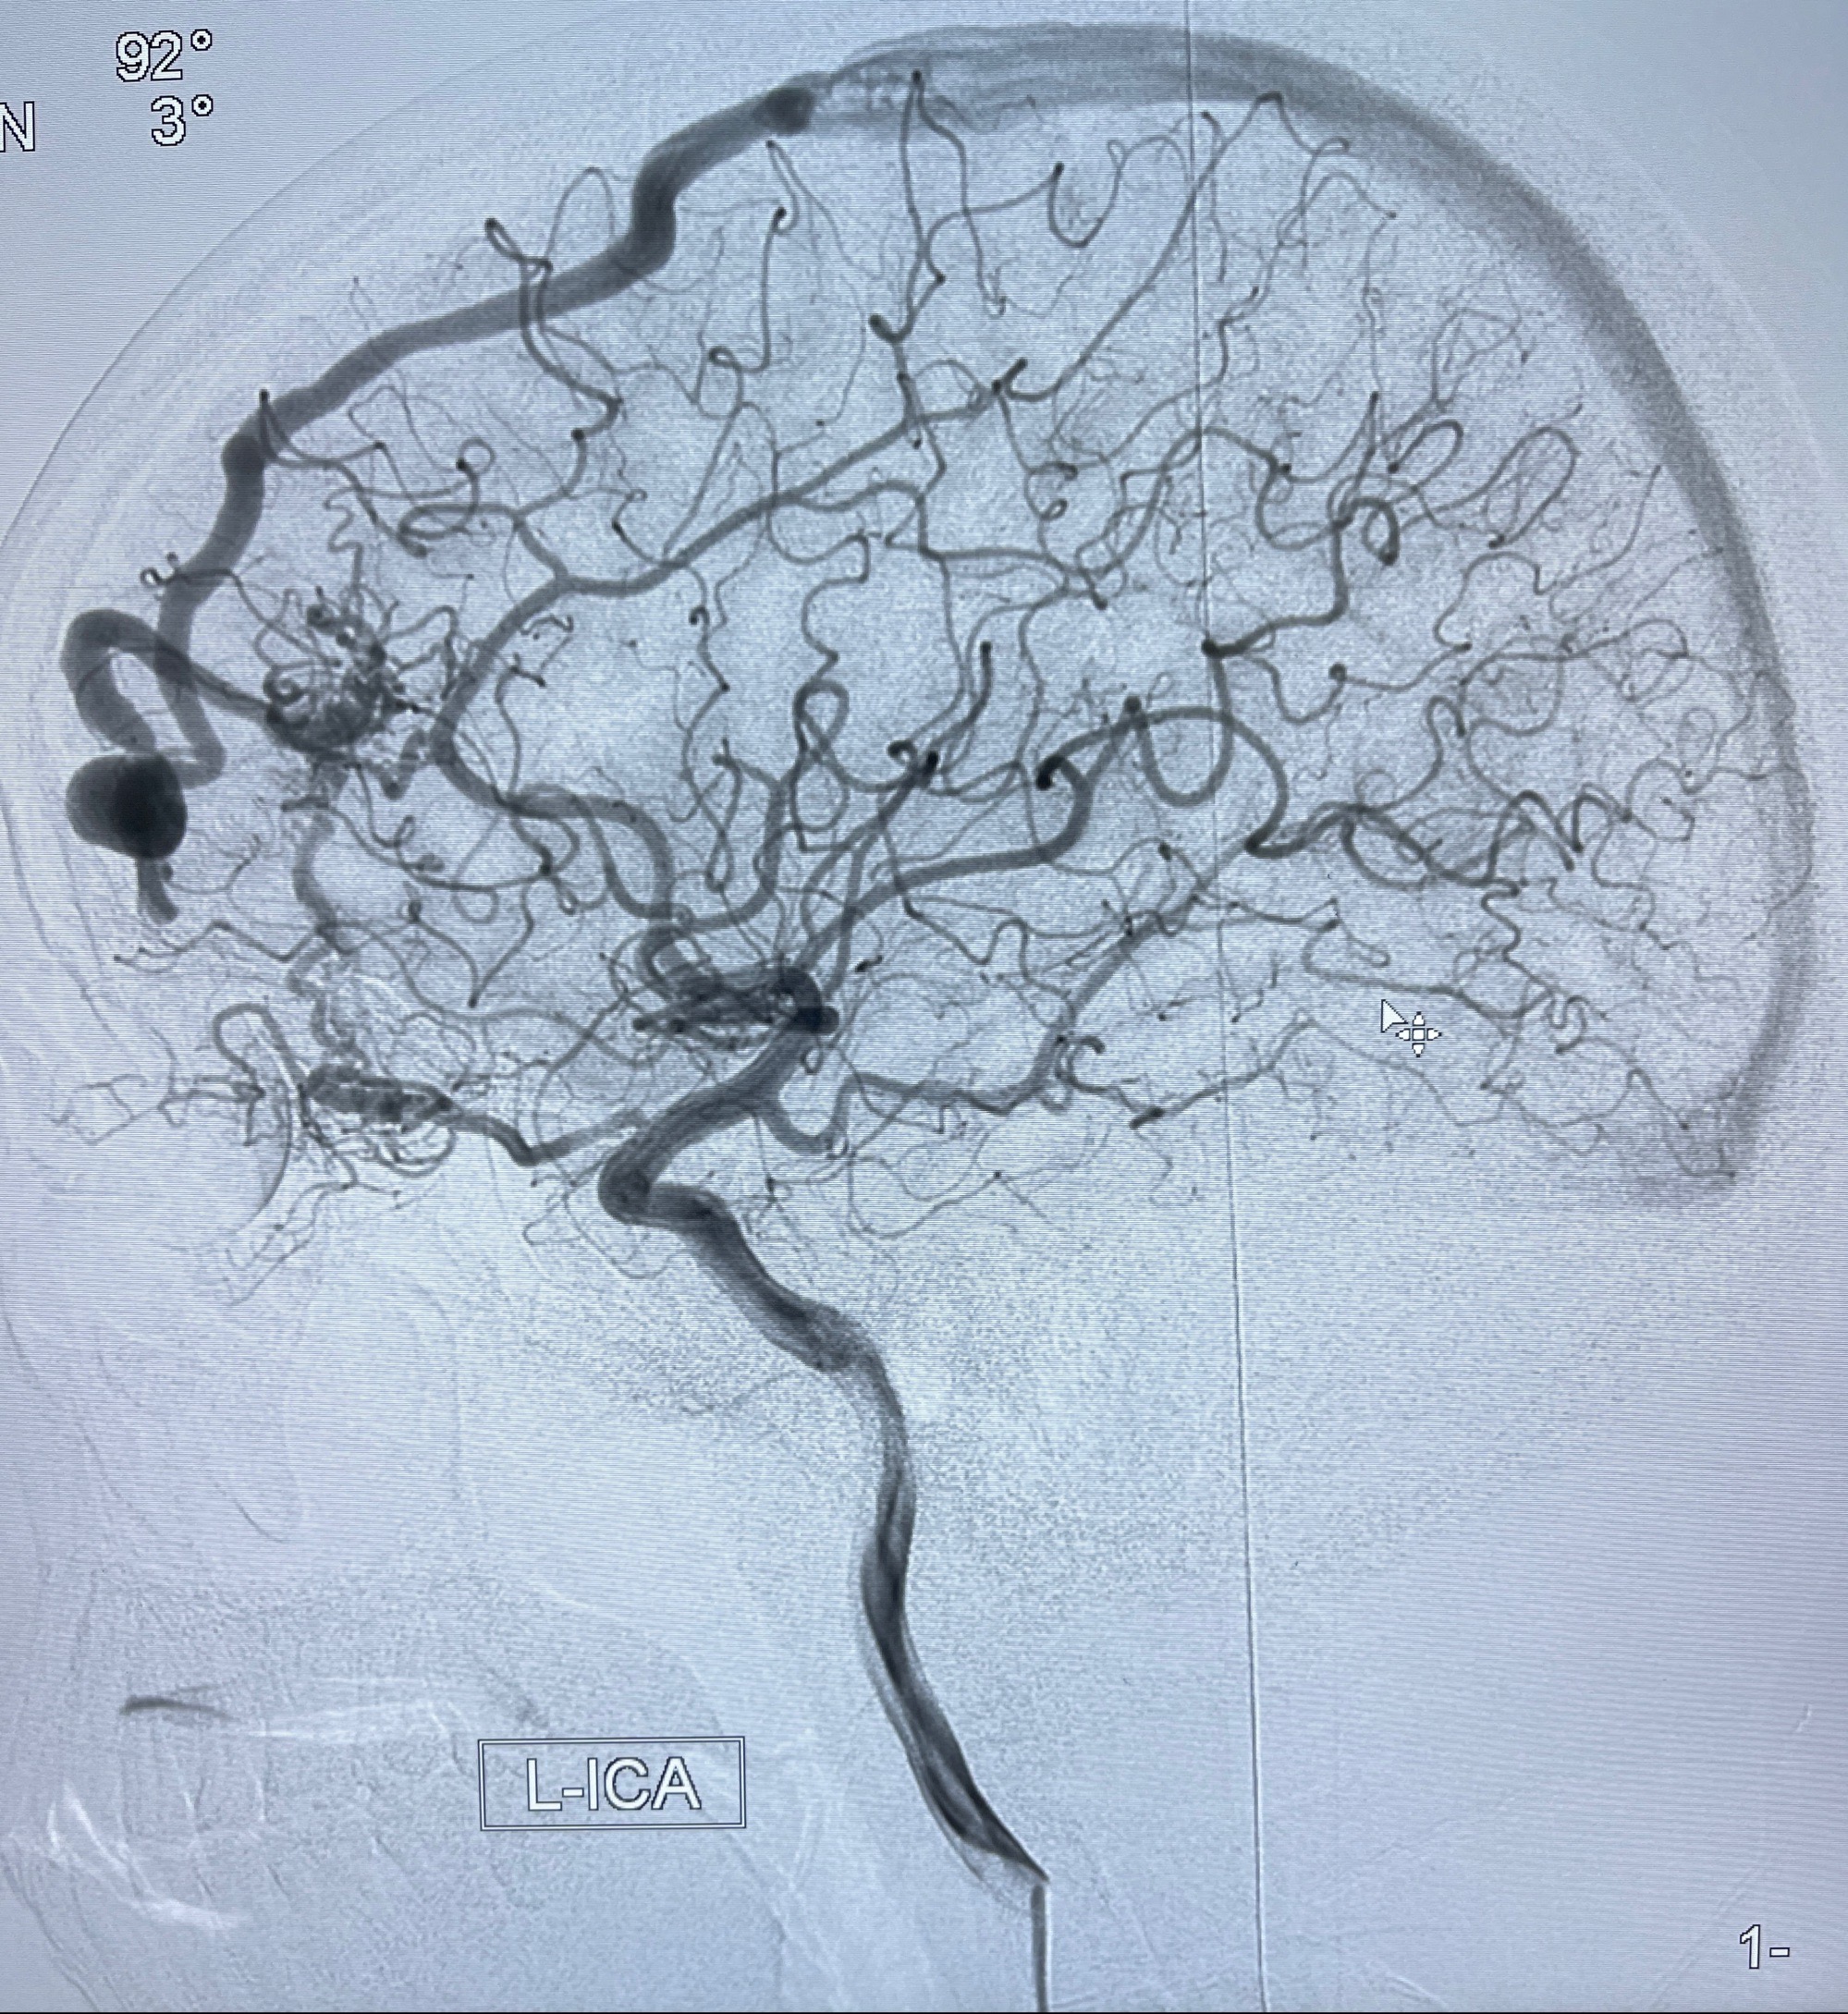

2023年8月21日]景德镇市第一人民医院脑血管造影检查,提示:主动脉弓、双侧颈总动脉、锁骨下动脉造影未见异常,左侧大脑前动脉静脉瘘。

2023-09-13全脑血管造影:前颅底硬脑膜动静脉瘘,供血动脉为双侧胼周动脉、眼动脉脑膜支,静脉向上矢状窦方向引流